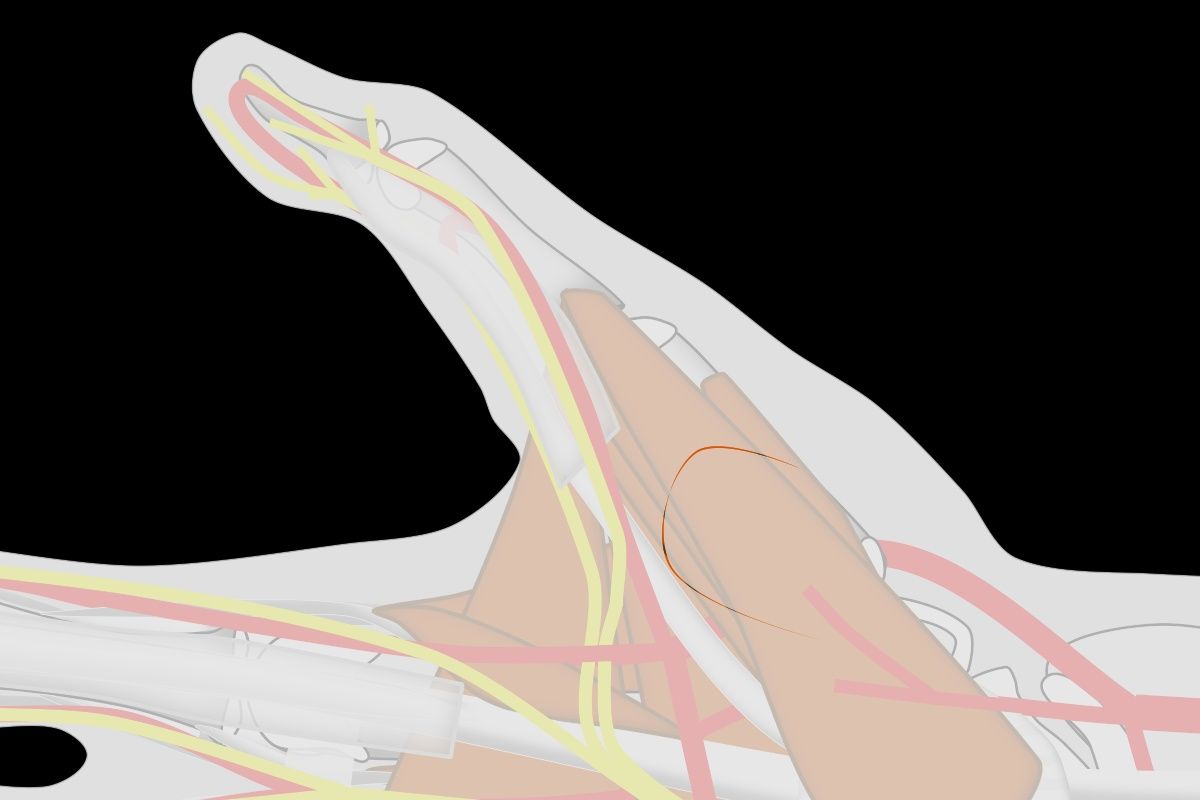

| A key issue is orienting the base of

the flap so that the flap comes to lie perpendicular

to the recipient site. This is best planned

in reverse using a template. This is helpful to also

plan the orientation change resulting from donor site

closure. |

| In this design,

The donor defect is closed as a transposition flap,

making best use of transverse skin laxity in this

area. This rotates the final flap orientation. |

| The goal is to

position the flap against the recipient bed without

tension or torsion. In addition to proper alignment, two key points are: ¤ Adduct the thumb basal joint to bring the flap to the finger to reduce flap tension. ¤ Flex the finger MCP joint to reduce PIP flexion. |